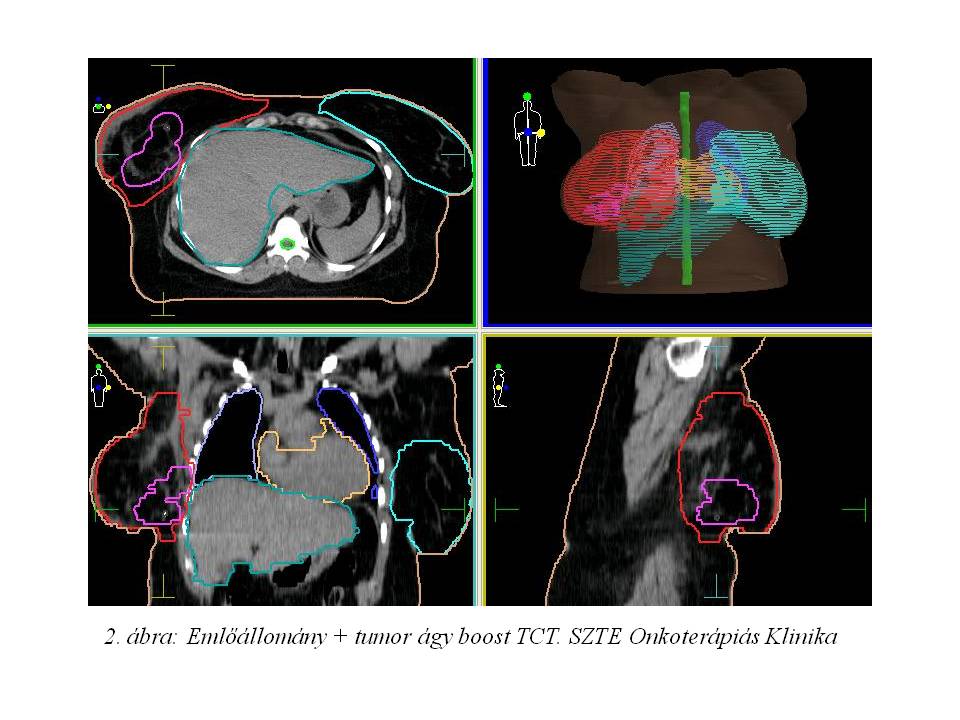

Fizikális vizsgálatakor a jobb emlőben az alsó negyedek határán, a bőrön behúzódást okozó, a mellkas fallal összekapaszkodó, fixált 3-3.5 cm átmérőjű tömött csomó volt tapintható. A mamillákon nem látszott eltérés, a nyirokrégiók szabadok voltak. Mammográfián (1. ábra) a tapintási eltérésnek megfelelően kb. 25 mm legnagyobb kiterjedésű, szabálytalan alakú, hangárnyékot adó, echo szegény képlet ábrázolódott. Emellett látótérbe került egy 11 mm-es, körülírt, echo szegény képlet is, valószínűleg sentinel nyirokcsomó. A látott képletekből UH vezérlés mellett citológiai mintavétel történt. Szövettani feldolgozás invasiv ductalis carcinomat véleményezett, mely hormon pozitív (ER: 50%, PR: 50%), HER-2 negatív. Staging vizsgálatként has-kismedence UH, mellkas RTG, csontscintigráfia történt, távoli disszemináció nem igazolódott.